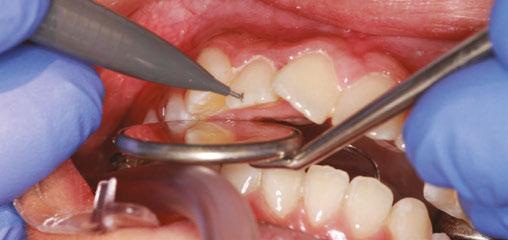

Treatment started with a transpalatal arch between the maxil lary first molars, which acted as a rigid unit to prevent unwanted facial inclination of the molars. A referral was made to an oral surgeon to remove the third molars. Fixed appliances of .022 x .028 Pinnacle® brackets with the McLaughlin, Bennett & Trevisi Prescription from Ortho Technology® were bonded to maxillary and mandibular teeth, and .014 thermal nickel-titanium fullform archwires (TruFlex®, Ortho Technology®, West Columbia, South Carolina) were used to align the arches after which a .016 stainless steel maxillary TruForce™ wire (Ortho Technology®) was placed. Following the stainless steel wire, two Vector TAS infrazygomatic miniscrews (Ormco™ Corporation, Orange, California) were inserted between the first and second maxillary molars (Figures 4A-4E).

Power chains with approximately 150 grams-force were added from the miniscrews to the maxillary first molars. After a .019 x .025 TruForce™ stainless steel archwire was placed in the maxillary arch, an additional power chain connected the maxil lary canines to the miniscrews to retract as well as to intrude the posterior buccal segments without jeopardizing the inclination of the maxillary anterior teeth. The patient refused the use of miniscrews in the mandibular arch, so molar bite blocks (Reli ance® Ultra Band-Lock, Ortho Technology®) controlled the ver tical position of the mandibular molars, which prevented them from over One-eightheruption.inch

vertical elastics (Amber medium 1/8 inch Manta Ray®, Ortho Technology®) and Class II 3/16 inch medium elastics (3/16 medium Sea Otter®, Ortho Technology®) were employed in the last stages of treatment to settle the occlusion and to improve the mandibular incisor inclination (Figures 5A-5C).